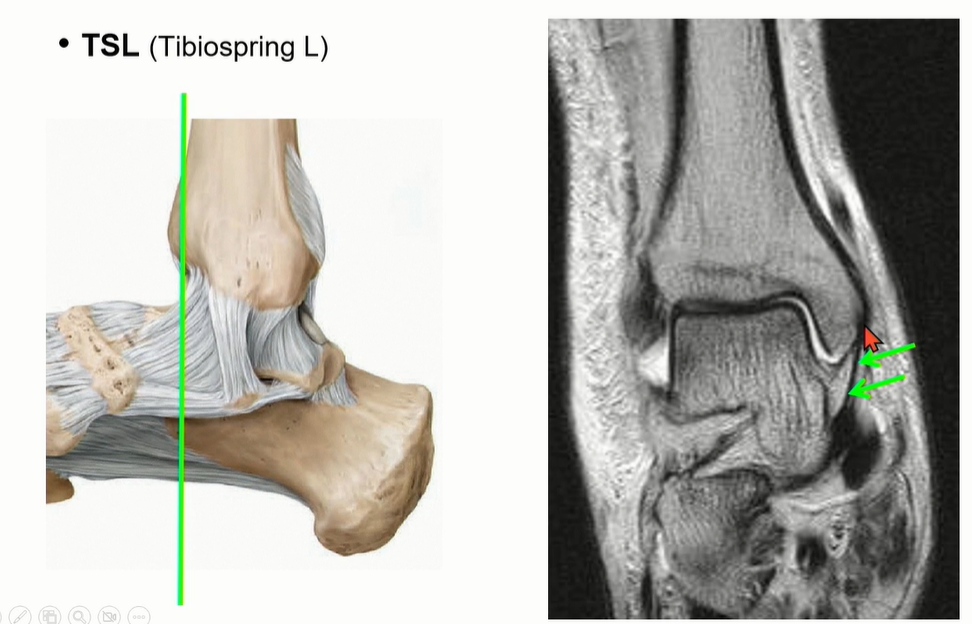

Tibiospring ligament는 Deltoid ligament의 superficial ligament의 2번에 해당.

spring ligament에 붙는다.